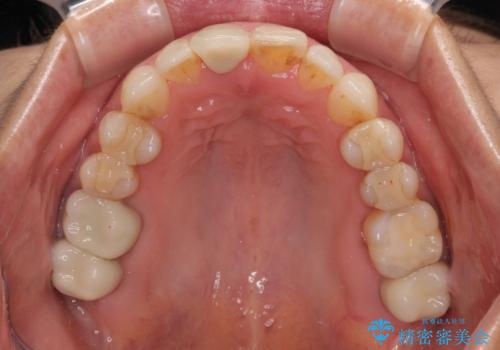

デコボコと銀歯 矯正治療とセラミック治療で綺麗な口元に

- 前歯のデコボコと口を開けたときに見える銀歯を気にして来院された患者様です。

ある程度デコボコが解消されれば大丈夫とのことで、インビザライン・モデレートパッケージを利用して歯列を整えて行くこととしました。

矯正治療後に銀歯をセラミッククラウンなどに置き換えていくと、どうしても後戻りを起こしてしまうため、矯正治療が概ね終了した時点で銀歯を全てセラミックとし、最後に仕上げでインビザラインにを用いて細かいデコボコを改善していくこととしました。

とても明るい口元となり、人目を気にせず、大きく口を開けて笑えるようになりました。